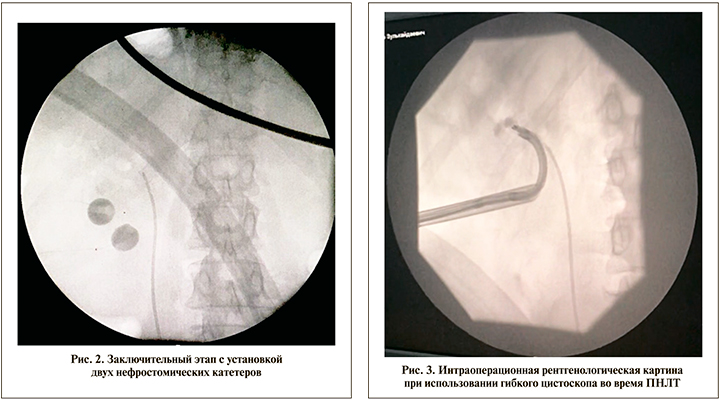

Мочекаменная болезнь (МКБ) – одна из самых актуальных проблем современной урологии. По данным О. И. Аполихина и соавт. [1], абсолютное число зарегистрированных больных МКБ в РФ с 2002 по 2009 г. увеличилось на 17,3%. Рост данного показателя в 2009 г. по сравнению с 2008-м составил 3,5% (с 502,5 до 520,2 на 100 тыс. населения). Отдельного внимания заслуживает коралловидный нефролитаз. Коралловидный камень – ветвящийся конкремент, парциально или полностью заполняющий почечную лоханку и чашечки почки [2]. По сравнению с другими формами МКБ коралловидный нефролитиаз быстрее приводит к истончению паренхимы органа и последующей почечной недостаточности [3]. «Золотым» стандартом лечения этой группы пациентов служит перкутанная нефролитотрипсия (ПНЛТ). По данным [4], при ПНЛТ, используемой как монотерапия, показатель SFR (stone free rate – уровень освобождения от камня) составляет лишь 56,9%. В зависимости от размера и сложности конфигурации конкремента эффективность ПНЛТ варьируется от 55 до 98% [5]. В связи с низким показателем SFR, который является критерием успешности операции, в настоящее время применяют различные подходы, его повышающие. Один из них – комбинация ПНЛТ с дистанционной ударно-волновой литотрипсией (ДУВЛ) («sandwich»-терапия). Результат исследования, проведенного в 1997 г., показал, что ПНЛТ с последующей ДУВЛ 2/3 пациентов обеспечивает полное избавление от камней [6]. Ко второму доступу (мульти-ПНЛТ) в полостную систему почки, как правило, прибегают при неэффективности гибкой нефроскопии или при крупном резидуальном фрагменте, локализующемся в противоположной относительно первичного доступа группе чашечек, а также при сложной конфигурации крупного конкремента. Данная методика также повышает SFR [7, 8]. На рис. 1, 2 показана интраоперационная рентгенологическая картина при выполнении двойного доступа в почку и завершающий этап операции, в ходе которого, как правило, устанавливали нефростомический дренаж в каждый пункционный ход. Это уменьшает риск послеоперационного кровотечения за счет механической компрессии сосудов почки.

Уретерореноскопия в сочетании с ПНЛТ до недавнего времени не имела большой популярности, но в связи с технологическими достижениями данный вид комбинированного лечения стал более широко использоваться при лечении коралловидного нефролитиаза. Так, С. Marguet et al. [9] показали, что использование этой комбинации по сравнению с мульти-ПНЛТ обеспечивало более высокий уровень SFR и меньший объем кровопотери. В зависимости от оснащенности клиники ПНЛТ можно проводить с использованием гибкого и ригидного нефроскопов. Интраоперационная картина с использованием гибкого цистоскопа представлена на рис. 3, 4. Как правило, применяя гибкий цистоскоп, возможно проведение полноценной ревизии полостной системы почки и полной литоэкстракции. Причиной невозможности выполнения полной ревизии и удаления всех фрагментов камня с помощью фиброцистоскопа, по нашему мнению, служит большой диаметр изгиба дистального конца инструмента, что исключает возможность ревизии параллельно расположенных чашечек почки.